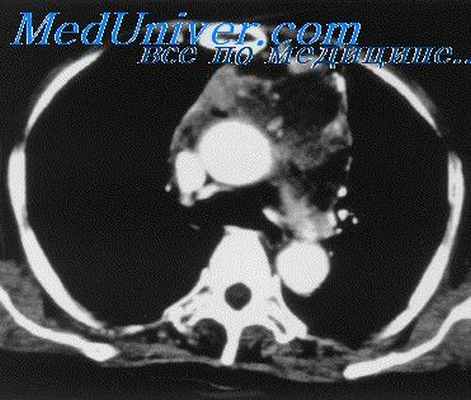

На компьютерной томограмме верхнего средостения на уровне III грудного позвонка определяется тень увеличенной щитовидной железы размерами: правая доля — 6,0 х 4,5 см,

Рис. 1. Рентгенограмма верхнего средостения в прямой проекции.

Загрудинный кольцевидный зоб. Контуры трахеи нечеткие.

Рис. 2. Компьютерная томограмма на уровне III грудного позвонка.

Щитовидная железа в виде кольца охватывает трахею и суживает ее. В обеих долях щитовидной железы кальцификаты и небольшие кистозные полости.

левая доля — 6,0 х 5,0 см. Контуры щитовидной железы неровные, бугристые, структура неоднородная с наличием каль- цификатов и небольших кистозных полостей (рис. 2). Денси- тометрические показатели железы снижены от +56 до + 84 ед. Ни. Щитовидная железа в виде кольца охватывает трахею, диаметр ее просвета сужен больше, чем наполовину. При реконструкции томографических срезов длина правой доли 11,0 см, левой— 10,5 см. Таким образом, нижний полюс щитовидной железы заходил за край яремной вырезки на 7 см (загрудинный зоб). На операции эти данные подтвердились полностью (рис. 3).